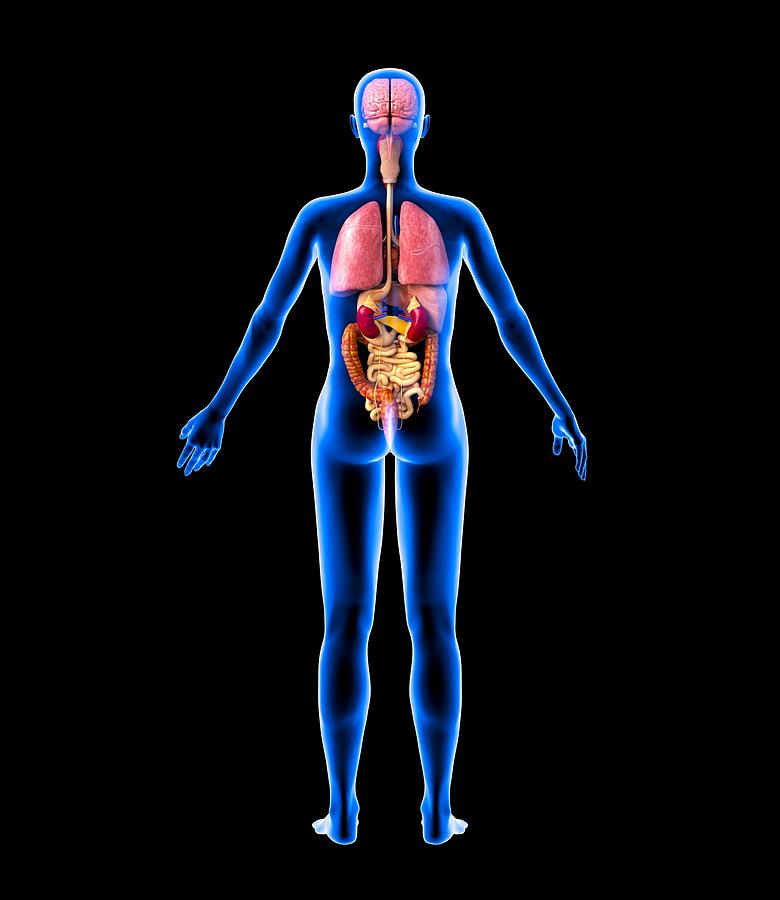

Anatomy Of Internal Organs Female – Organ Anatomy Female Anatomy …

Right Side Women’s Body Human Body Organs / Human Anatomy And …

Female Body Organs Diagram Anatomy | MedicineBTG.com

Human Anatomy Picture Organs Female Human Body Diagram Of Organs See …

Right Side Women’s Body Human Body Organs : What Do Right-Sided Organs …

Female Human Organs Diagram | MedicineBTG.com

Internal Organs Adult Female Front And Back View Stock Photo – Download …

Illustration Of Female Internal Organs Photograph by Science Source

Illustration Of Female Internal Organs Photograph by Science Source

Illustration Of Woman\’S Internal Organs / Internal Human Organ Ovaries …

Human Female Organ Diagram . Human Female Organ Diagram Colorful Human …

Female Internal Organs, Artwork Photograph by Roger Harris